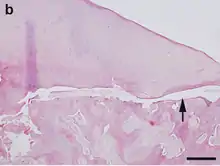

Pathological specimen from a sow— the arrow points to a fracture in the lateral epicondyle of the humerus.

Hematoxylin and eosin staining. Bar = 200 μm.

OCD also is found in animals, and is of particular concern in horses, as there may be a hereditary component in some horse breeds.[97] Feeding for forced growth and selective breeding for increased size are also factors. OCD has also been studied in other animals—mainly dogs, especially the German Shepherd[98]—where it is a common primary cause of elbow dysplasia in medium-large breeds.[99]

In animals, OCD is considered a developmental and metabolic disorder related to cartilage growth and endochondral ossification. Osteochondritis itself signifies the disturbance of the usual growth process of cartilage, and OCD is the term used when this affects joint cartilage causing a fragment to become loose.[100]